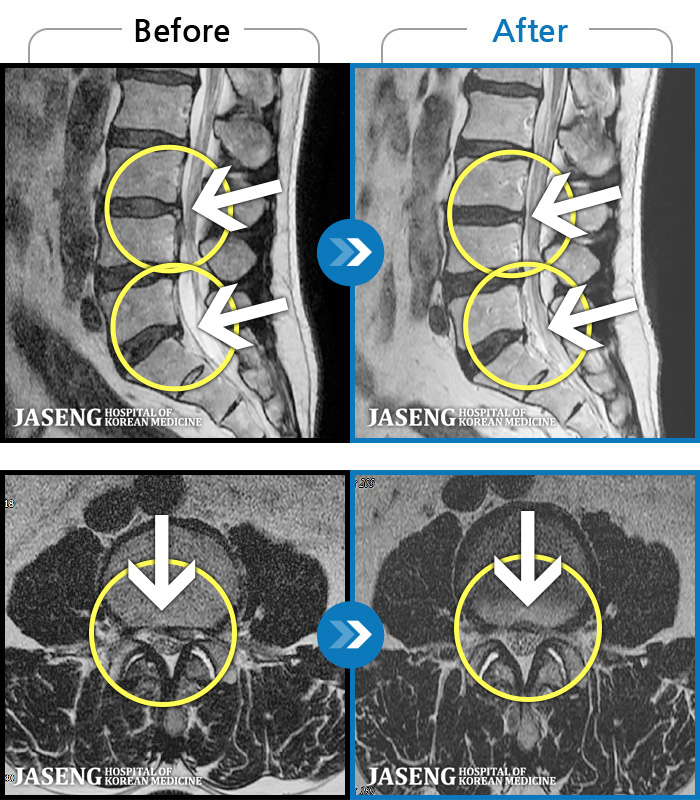

ȯںп Ǹ ǿ ԿǾ, ο ġ ۿ Ƿ ġḦ Ͻñ ٶϴ.